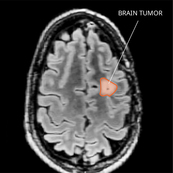

PXA MRI

PXA / APXA

Pleomorphic xanthoastrocytoma (PXA) and anaplastic pleomorphic xanthoastrocytoma (APXA) tumors can be slow- or fast-growing tumors in the central nervous system. They occur most often in young adulthood. Learn more about PXAs and APXAs.